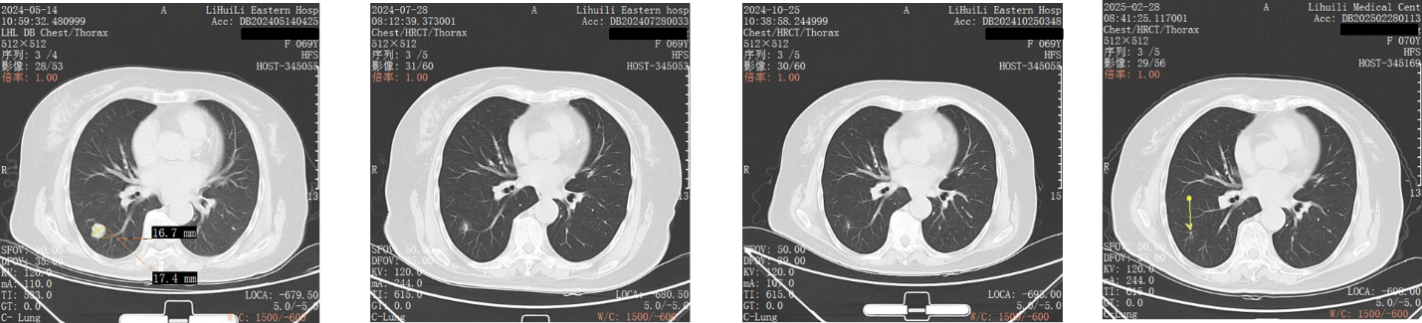

疗效评价:治疗 6 周期后,胸部 CT 示双肺转移瘤较基线明显缩小(较大者从 20×15mm 缩小至 10mm 以下),右乳肿块缩小至 1cm 以下,右腋下淋巴结消失,疗效评价为部分缓解(PR)。

疗效评价:2025 年 2 月 28 日胸部 CT 示双肺转移瘤完全消失,右乳未探及肿块;2025 年 3 月 21 日乳腺超声示右腋下无肿大淋巴结,疗效评价为CR。

图3胸部CT(右左至右:2024年5月14日、2024年7月28日、2024年10月25日、2025年2月28日)